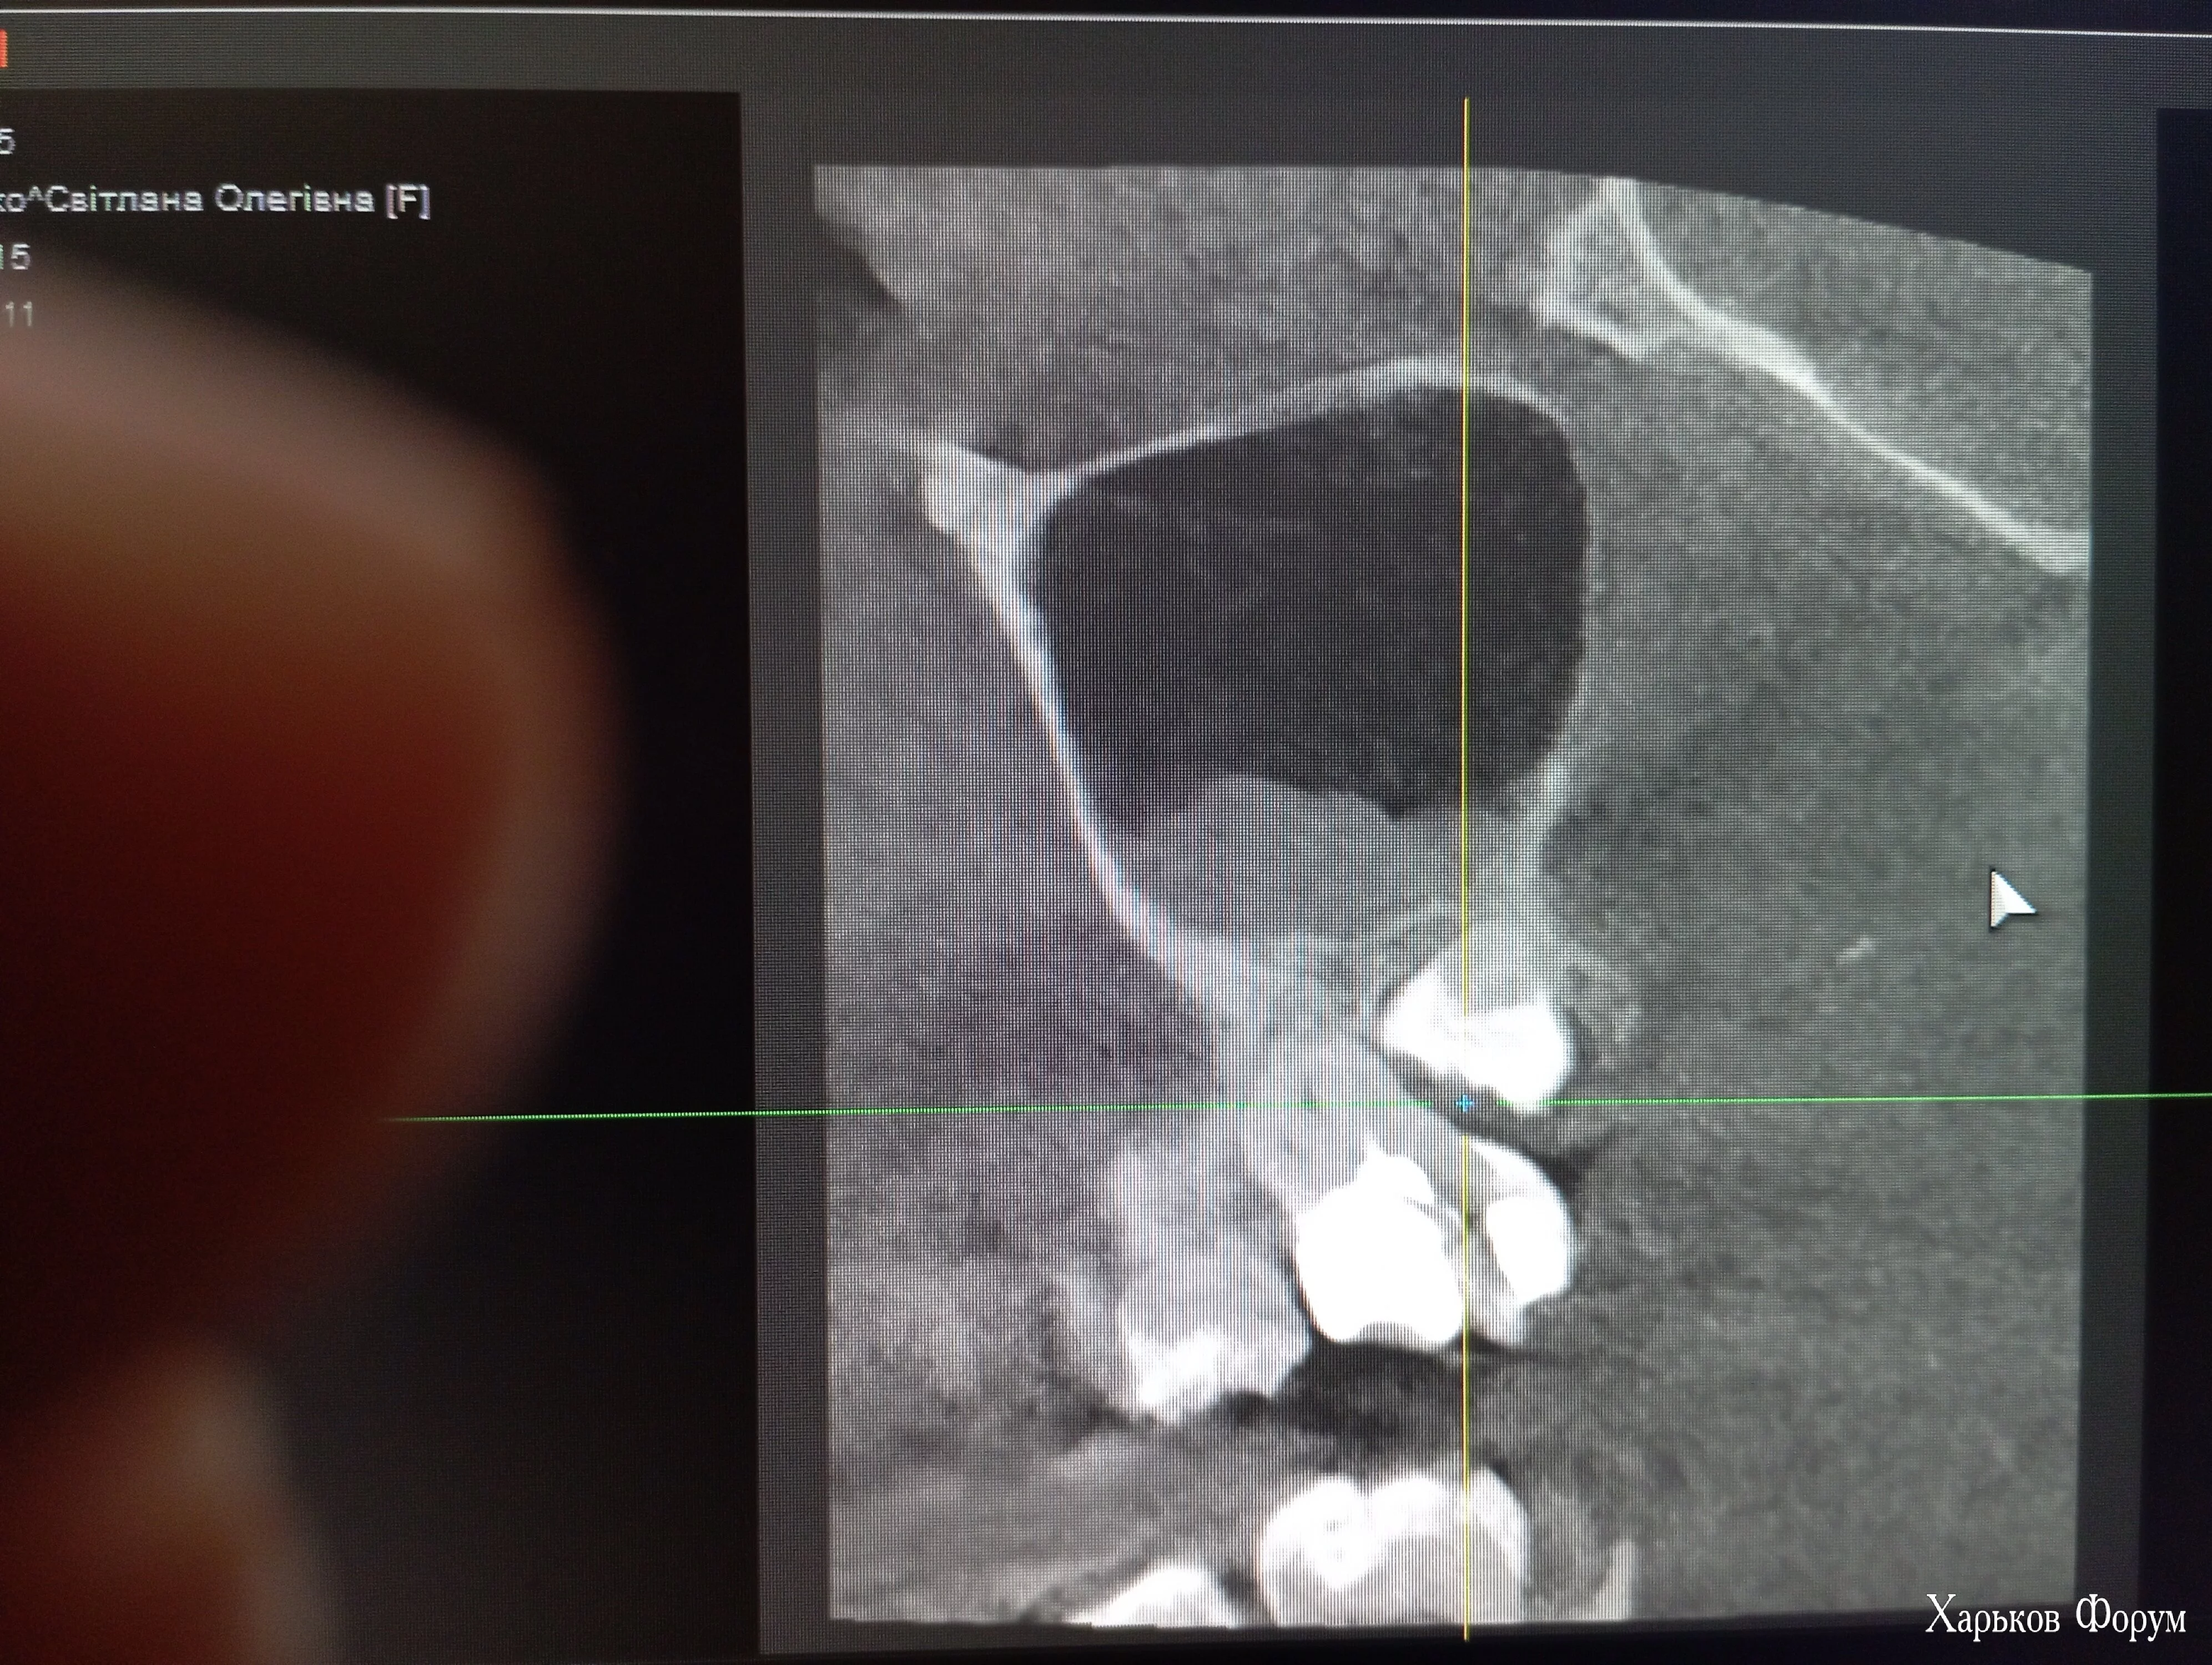

Добрый день, уважаемые доктора! Прошу помощи по консультации для жены. Проблема с 8й справа вверху, начало поднывать в данной области. КТ показало необходимость удаления, возможно и соседних. Мнения хирургов разнятся сильно: 1. удаление только 8 (6 и 7 лечим). 2. Удаление 8 и 7, 7 все равно не спасти. 3. Удаление трех зубов - 6, 7 и 8, 6ку нужно удалить типа чтоб не оставлять очаг инфекции, типа там гранулема. Также мнения сильно отличаются где это делать: 1. Только стационар, по общим наркозом, с подшиванием возможной перфорации гайморовой лоскутами из поднебья (челюстно лицевой хирург очень опытный). 2. В частном кабинете, с подшиванием тоже, я так понял лунки, каким точно подшиванием не знаю, типа это рутина для врача (хирург-стоматолог врач тоже суперопытный, с заграничными практиками, современным кабинетом). Снимки пробую прикрепить ниже. Уважаемые доктора, скажите пжл, шо тут делать, где и как ??? Нужен ли тут стационар с общей анастезией или нет ? От мнений голова кругом... А то уже капец, еще и маленький ребенок на руках.... Хоть бери и изучай ваши протоколы (или забугорные) и жене оперируй :) Фамилий понятно не называю, этику вашу понимаю

Ссылка на диск с КТ.

Фото

Вкладення

• IMG_20240116_140701_794.webp

IMG_20240116_140701_794.webp

1.1 MБ · Перегляди: 85

• IMG_20240116_140700_222.webp

IMG_20240116_140700_222.webp

1.5 MБ · Перегляди: 88

• IMG_20240116_140701_004.webp

IMG_20240116_140701_004.webp

910.1 КБ · Перегляди: 87

• IMG_20240116_140700_625.webp

IMG_20240116_140700_625.webp

1.3 MБ · Перегляди: 91

• IMG_20240116_124652.webp

IMG_20240116_124652.webp

1.8 MБ · Перегляди: 93